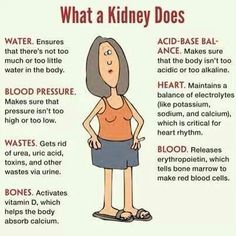

7. The Excretory System (human)

- Excretory organs and their functions e.g. kidney, skin and lungs.

- The process of excretion.

- Waste materials of excretion e.g. carbon (iv) oxide, sweat and urine.

- Need for excretion.